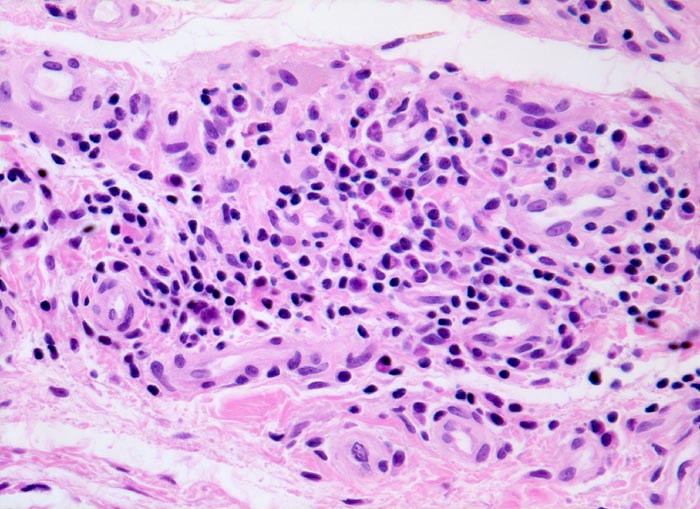

Typische histologische Veränderungen sind eine synoviale Zottenhyperplasie, Verbreiterung der Deckzellschicht unter Einschluss mehrkerniger Riesenzellen, Fibrinexsudate und synoviale Ulzerationen, Infiltrate von Lymphozyten teils in Form von Lymphfollikeln, Plasmazellen, neutrophilen Granulozyten, Makrophagen und Siderophagen, sowie Einschlüsse von Knorpel- und Knochenfragmenten (Detritussynovialitis). Die histologischen Befunde der Synovialis korrelieren oft nicht mit den klinischen Angaben. Trotz fortgeschrittener Gelenkdestruktion mit ausgeprägter klinischer Symptomatik können Synovialektomiepräparate nur sehr geringe pathologische Veränderungen zeigen. Oft ist auch nicht mehr zu eruieren, welche Läsionen Folge der Grundkrankheit und welche Folge diverser intraartikulärer Therapien oder begleitender Superinfektionen sind.

Bei einem grösseren Teil der Gelenkerkrankungen ist die histopathologische Diagnostik dadurch eingeschränkt, dass nur uncharakteristische Befunde zu erheben sind. Um die Synovialitisdiagnostik zu standardisieren, wurde ein Gradierungssystem, der sog. Synovialitis-Score, vorgeschlagen. Gradiert werden die Dicke der Deckzellschicht, die Zelldichte des synovialen Stromas und das chronische Entzündungsinfiltrat. (0-1 Punkt: keine Synovialitis; 2-4 Punkte: low-grade Synovialitis; 5-9 Punkte: high-grade Synovialitis). Der Befund einer hochgradigen Synovialitis als diagnostisches Kriterium für eine rheumatische Erkrankung besitzt eine Sensitivität von 60.5% und eine Spezifität von 95.5%. Die diagnostische Synovialisbiopsie bleibt aber ausgewählten und klinisch unklaren Konstellationen vorbehalten und ist in der Mehrzahl der Fälle nicht erforderlich.

Innerhalb der high-grade Synovialitiden (histologischer Synovialitisscore >4) ist eine sichere Unterscheidung zwischen Psoriasisarthritis, reaktiver Arthritis und rheumatoider Arthritis rein histologisch nicht möglich, es sei denn, es liegen Rheumagranulome vor. Entscheidend für die integrative Diagnose sind daher auch klinische und serologische Befunde. Typische histologische Befunde können die klinische Diagnose aber unterstützen.

• Herdförmig Fibrinauflagerungen durchsetzt von neutrophilen Granulozyten.

• Hyperzelluläres Stroma mit lymphoplasmazellulärem Entzündungsinfiltrat mit Ausbildung von Lymphfollikeln.